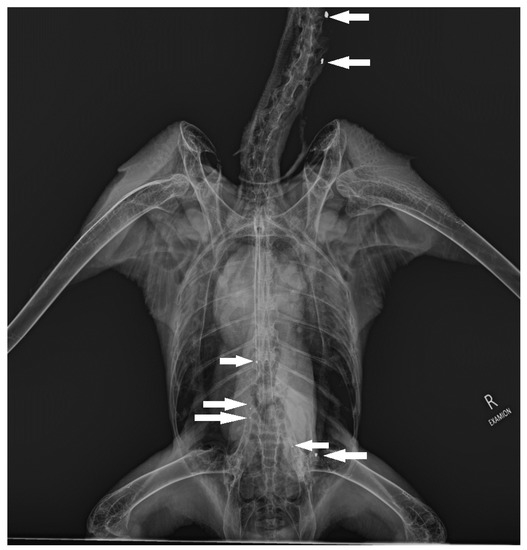

2.1. Sample Collection and Preparation